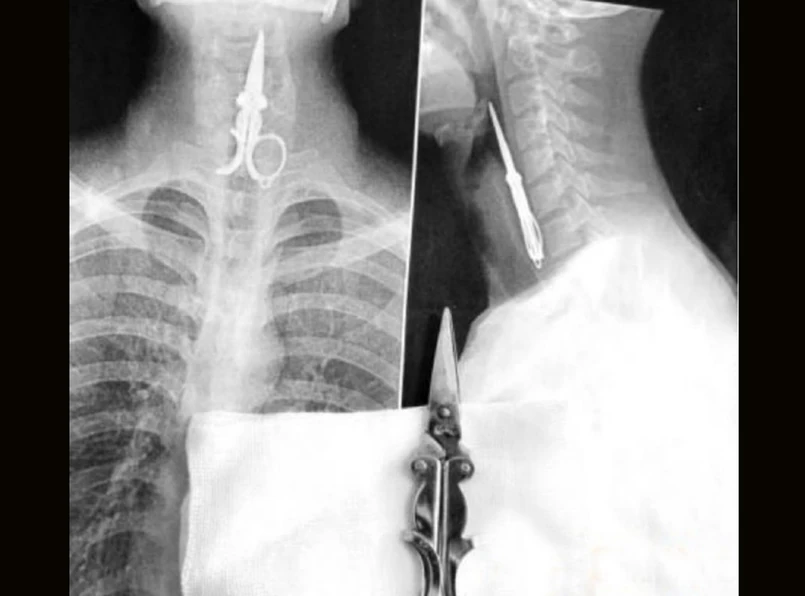

Chińscy chirurdzy uratowali mężczyznę, który niechcący wciągnął parę nożyczek do swego gardła. Jak to zabójcze narzędzie znalazło się w jego ustach? Otóż sprytny chińczyk próbował wyczyścić sobie nimi zęby.

Norzyczki utknęły Lin Kongowi w gardle z powodu dowcipu. Pewnie nic by się nie stało, gdyby czyścił zęby w samotności. Niestety, toważyszył mu przyjaciel, który podczas kuracji opowiedział dowcip. Na nieszczęście, był on tak śmieszny, że śmiejąc się, pan Lin wciągnął norzyczki do gardła. Próbował je wyciągnąć, lecz swoimi wysiłkami sprawił, że mordercze narzędzie ugrzęzło jeszcze głębiej. Nie było innego wyjścia, musiał jechać do szpitala.

„Gdy przybył do nas, skręcał się z bólu, był biały jak prześcieradło i cały czas pluł krwią” - opowiada doktor Chen Wei, chirurg ze szpitalu w Putian we wschodnich Chinach. Na zdjęciu rentgenowskim dokładnie widać nożyczki tkwiące w gardle, na szczęście czubkiem do góry. Niestety nie można było znieczulić pacjenta, żeby je wyciągnąć, gdyż spowodowałoby to rozlużnienie krtani, a wtedy przedmiot mógłby wpaść jeszcze głębiej. Narzędzie wyciągnieto po 30 minutach, na szczęście dla pana Lina, jego krtań nie została mocno poraniona.